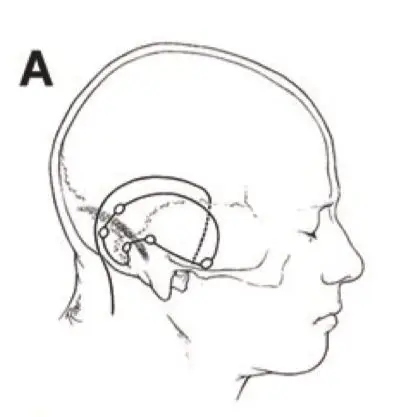

岩斜区位于颞骨岩部背面与枕骨斜坡部的岩斜裂汇合处,从岩骨尖至颈静脉孔。内侧至斜坡中线,外侧至第Ⅴ、Ⅶ和Ⅷ脑神经,上缘为鞍背,下缘为颈静脉孔水平;下方为枕骨大孔区。岩斜区脑...